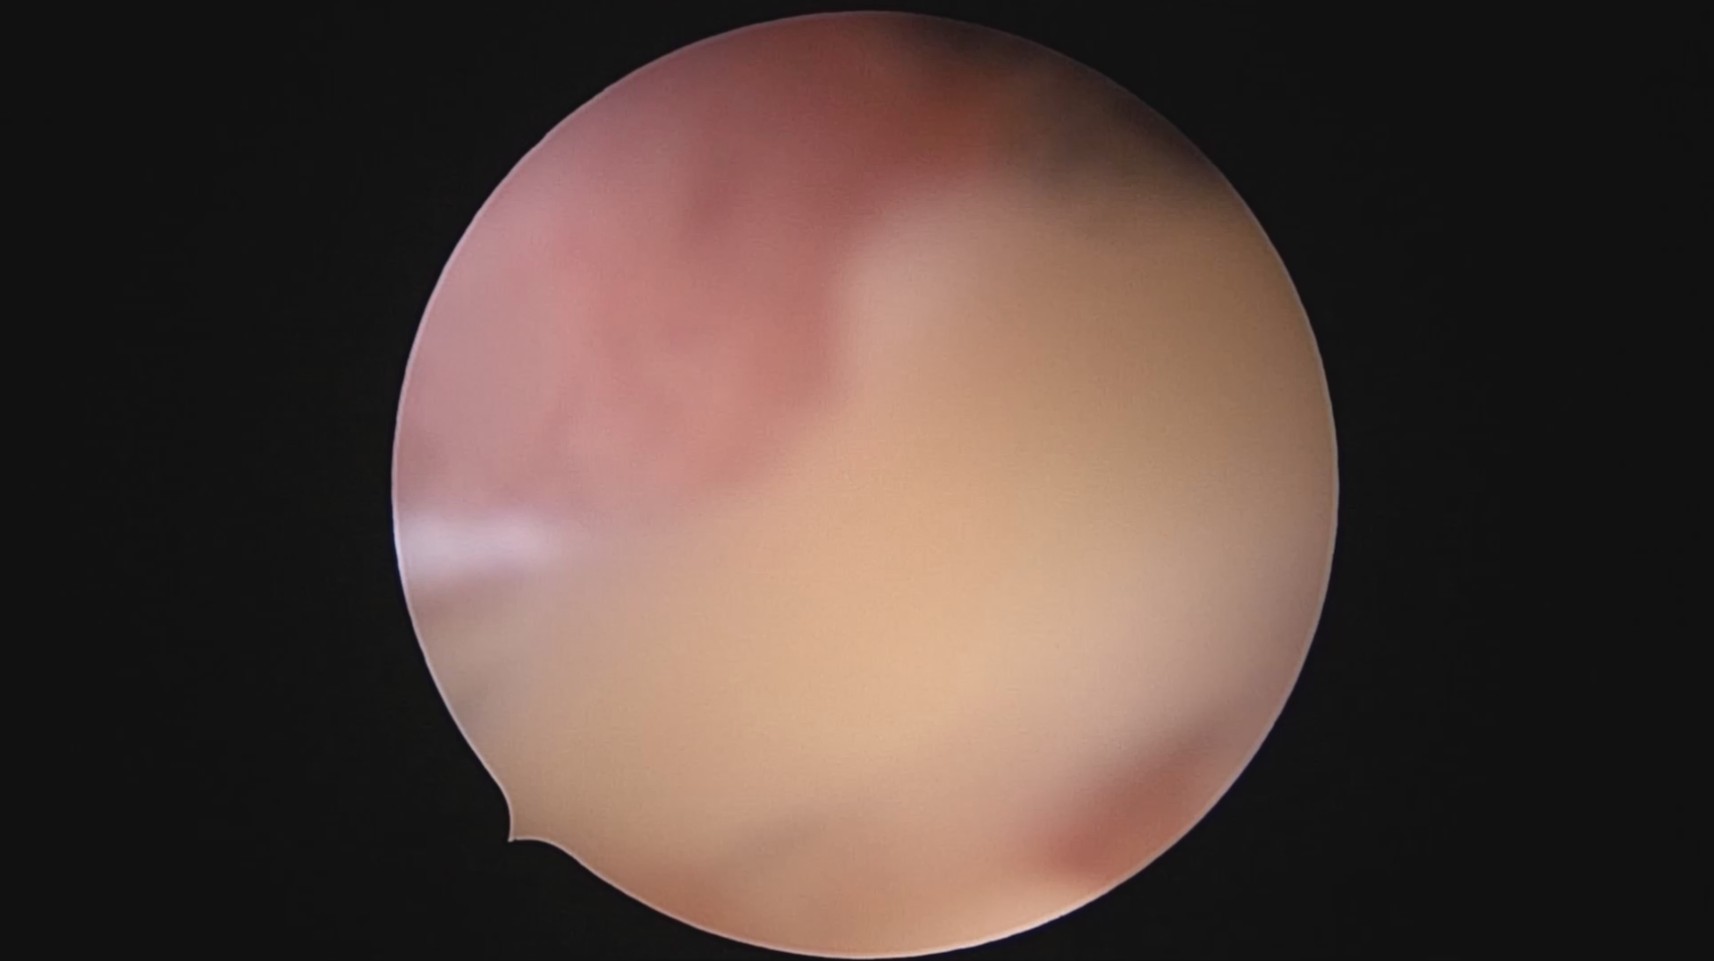

患者28岁,G7P3,顺产3次,完全纵膈子宫,单宫颈。2015年、2018年顺产,2019年左侧宫腔计划外妊娠行宫腔镜取胚及左侧宫腔放置γ环(推测既往妊娠左侧宫腔妊娠可能性大)。2023年4月带环受孕(应该为右侧宫腔妊娠),2023年12月足月阴道分娩,分娩时试图取出左侧宫腔内节育器,因操作困难,取环失败。2024年2月顺产后67天,要求取出宫内节育器,左手臂放置皮埋避孕棒。B超提示环距宫底1.1cm,环两翼分别距子宫前壁浆膜面0.4cm,距子宫后壁浆膜面0.3cm。宫腔镜术中膨宫困难,见宫颈管及宫腔少许淡黄色脓液流出,γ环逆时针旋转约80度,两臂指向左侧宫腔前后壁(2019年放置环时亦如此,因单侧宫腔前后径大于横径所致)。异物钳取出节育环,左右侧宫腔均见散在黄色机化组织,未取病检。